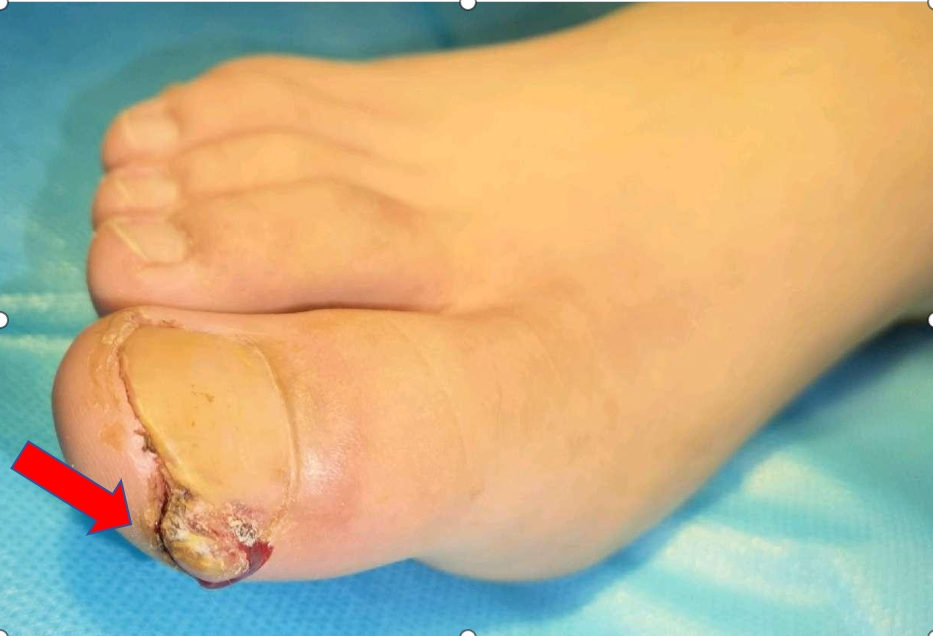

而局部反复发炎,会导致肉芽组织增生,就像下图箭头指向的部位。

导致慢性甲沟炎最常见的病因就是嵌甲。嵌甲是指甲板侧缘长入侧甲廓深处、嵌入甲沟,导致局部红肿、疼痛、糜烂,反复刺激导致侧甲廓组织异常增生的一种疾病。简单来说就是脚趾甲长进了肉里,像一把小刀一样反复刺破皮肤,引起感染。